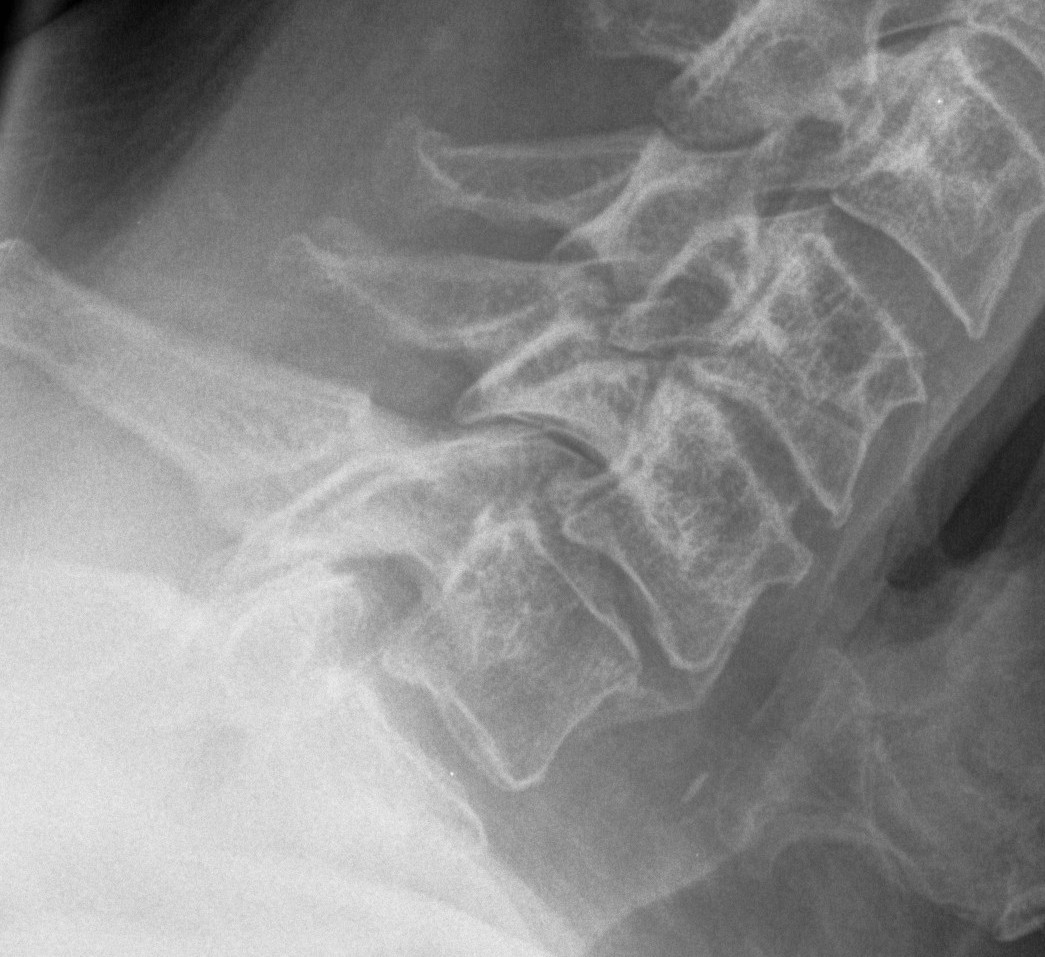

X-ray

Degenerative changes - C5/6 commonest level followed by C6/7

Alignment - lordosis v kyphosis

Ossification PLL

Flexion / Extension views show instability

- > 3 o

- > 11 mm

Torg-Pavlov's Ratio (A/B)

AP diameter of spinal canal (A) divided by the AP diameter of body (B) at same level

- should be 1.0

- < 0.8 is narrowed and stenotic